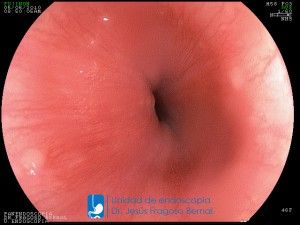

"La Unidad de Endoscopía se ha caracterizado por un progreso continuo desde su inicio marcando la pauta en los procedimientos endoscópicos en el estado de Tlaxcala y estando siempre a la vanguardia tecnológica."

Dr. Jesús Fragoso Bernal